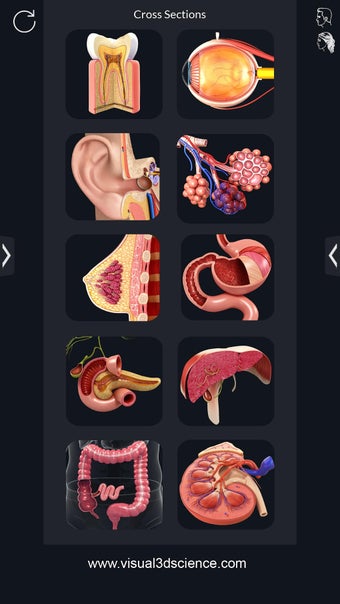

Je kunt alle informatie over de organen krijgen, inclusief hun locatie, hun functie en hoe ze eruitzien.